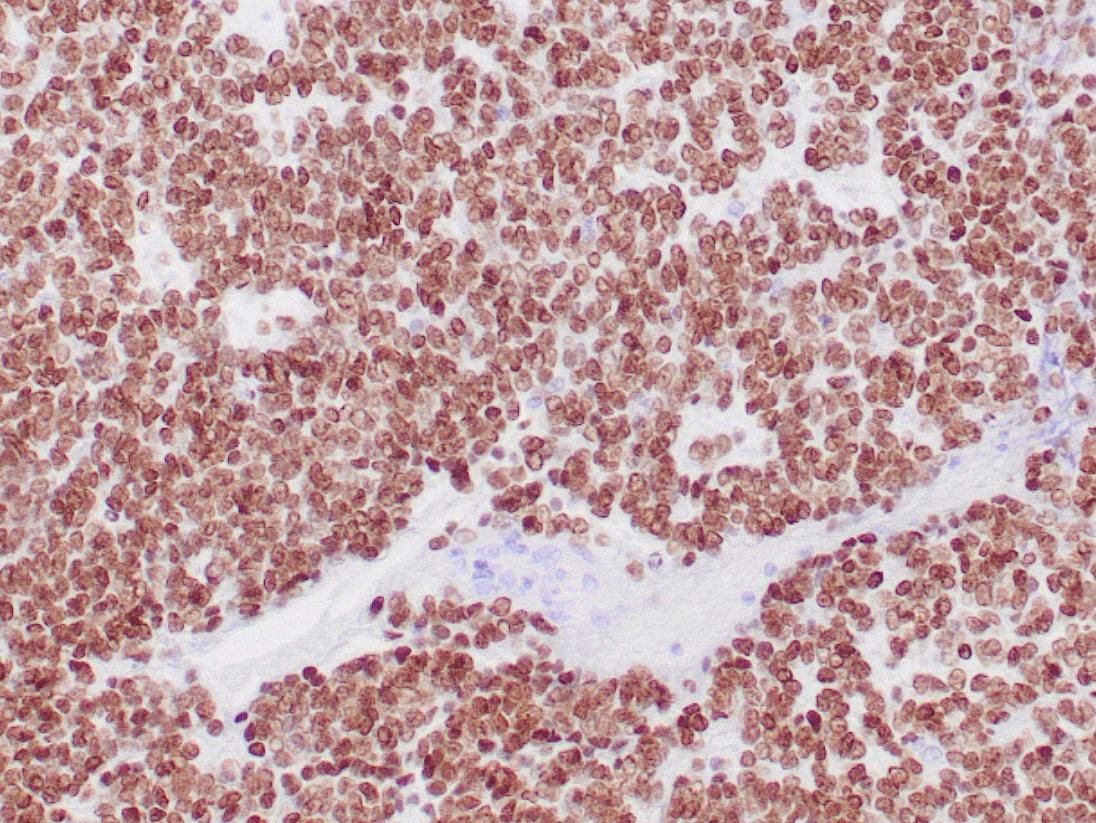

NKX2.2 ifadesinin bağırsak nöroendokrin tümörlerinde bulunduğu tespit edilmiş olup, bu da onu gastrointestinal nöroendokrin tümörlerin incelenmesi için potansiyel bir belirteç haline getirmektedir. Daha yakın zamanlarda, NKX2.2 proteini, Ewing sarkomuna özgü füzyon proteini olan EWS-FLI-1'in bir hedefi olarak tanımlanmış ve dizi tabanlı gen ekspresyon analizi temelinde Ewing sarkomunda farklı şekilde yukarı regüle edildiği gösterilmiştir. %93 duyarlılık ve %89 özgüllük ile Ewing sarkomu için değerli bir belirteç görevi görür ve küçük yuvarlak hücreli tümörlerin ayırıcı tanısında yardımcı olur.

BOYANMASI GEREKEN ALAN : Çekirdek

POZİTİF KONTROL : Ewing sarkomu